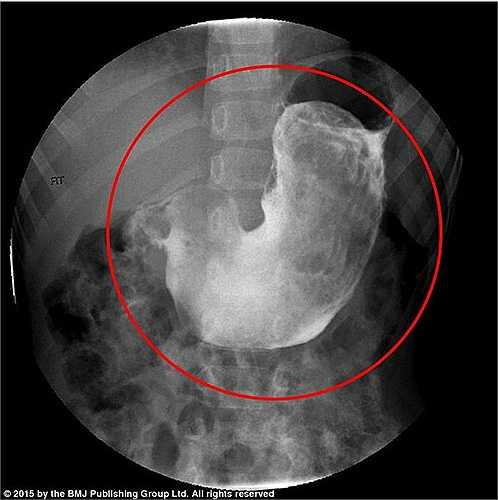

Sau khi khám sơ bộ, các bác sỹ phát hiện bụng bé gái chướng to, khi ấn có một khối to, chắc đang nằm trong ổ bụng của bệnh nhân. Hình chụp X quang dạ dày bệnh nhân cho thấy một khối vật thể lạ giống một búi tóc.

Bé gái được chẩn đoán mắc hội chứng Rapunzel, chủ yếu gặp ở những người trẻ bị rối nhiễu cảm xúc hoặc chậm phát triển tâm thần. Hội chứng này khá hiếm gặp, trên thế giới có khoảng 120 trường hợp và hầu như chỉ xảy ra ở phụ nữ trẻ.